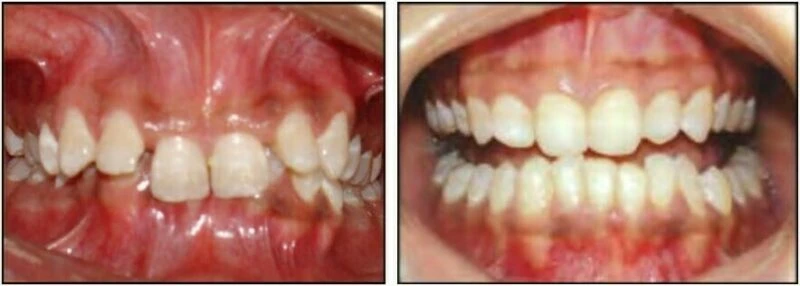

2.2 SAI KHỚP CẮN THEO MẶT PHẲNG ĐỨNG NGANG

Trường hợp này có thể chia làm hai phân loại tùy thuộc vào độ phủ theo chiều dọc của các răng giữa hai hàm.

Cắn sâu

Với loại này, độ cắn phủ theo chiều dọc giữa răng hàm trên và răng hàm dưới lớn hơn so với bình thường.

Cắn hở

Với loại này thì không có độ phủ hoặc chỉ có một khoảng trống giữa các răng hàm trên và hàm dưới khi bệnh nhân cắn lại ở khớp cắn trung tâm. Một trường hợp cắn hở có thể gặp ở răng trước hoặc răng sau.